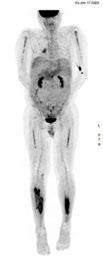

PETCT: interval reduction in metabolic activity at diffusely intense FDG uptake involving the axial and appendicular bones - good partial response

MRI & PET: Diffusely and focally hypermetabolic bone lesions in left 5th rib, both humerus, both scapulae, spines, both pelvic bones, both proximal fumora